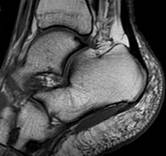

|

Рис. 4. Левый – полный разрыв задней малоберцово-таранной связки (стрелкой показана часть связки в точке фиксации к малоберцовой кости). Правый – гематома в зоне повреждения (×). |